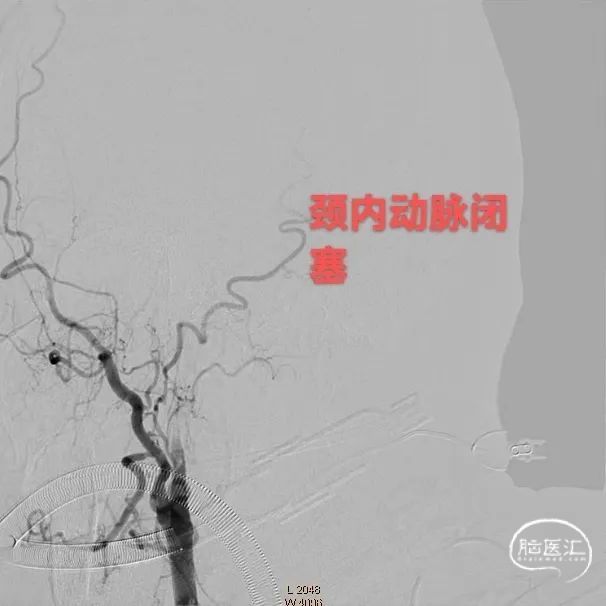

造影证实右侧颈内动脉闭塞。

左侧正侧位造影。

患者系缺血性卒中,在静脉溶栓时间窗内,排除禁忌症,给予阿替普酶静脉66.6mg溶栓,术前NIHSS 40分,mRS 4分,并完善头颈CTA,提示右侧颈内动脉闭塞,结合心电图,考虑心源性栓塞,建议急诊血管内治疗,结合辅助检查,考虑血栓负荷量较大,首选治疗方案为支架取栓,备选导管抽栓。